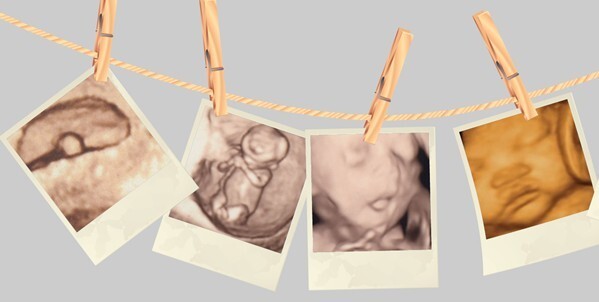

随着科技的发展,四维彩超登上了孕检的舞台。可是,四维彩超在孕检中到底起着哪些功效呢?福州台江医院妇产科医师来告诉你!

★四维彩超在孕检中起着哪些功效?

以上就是关于“四维彩超在孕检中起着哪些功效”的详细介绍。孕妈妈们一定不要忽略孕检的重要性,相对于B超来说,四维彩超给孕妈妈们提供更多的服务。欢迎孕妈妈们前来福州台江医院做四维彩超检查!